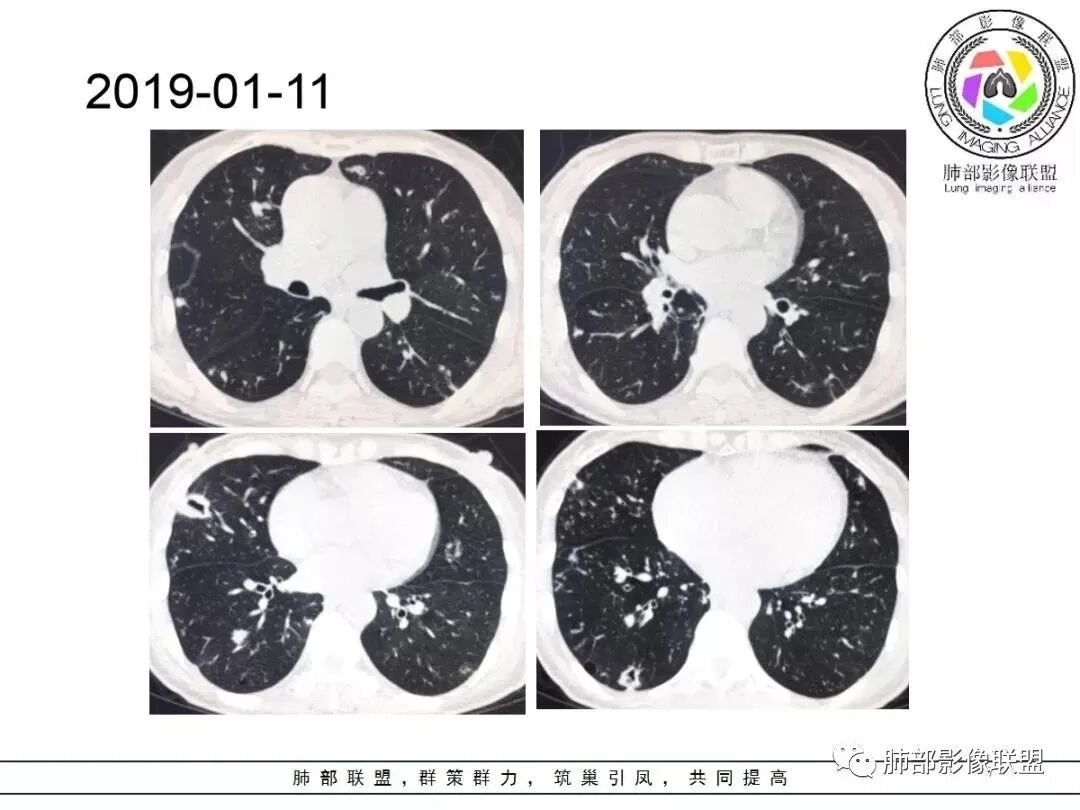

中年妇女,类风湿性关节炎病史,RF升高,感染性指标正常,双肺散在多发结节、斑片、条片灶,边缘欠清晰,大部分胸膜下分布,部分反晕,考虑RA-ⅠLD ,OP样改变

中年女性,有类风湿关节炎病史,双肺内及胸膜下见多发结节,条索状及小实变影,部分结节病灶垂直支气管血管束生长,部分结节病灶内见偏心性空洞形成,病灶收缩力弱,病灶形态多样,部分可见纤维化样改变,整体符合Op表现,结合患者病史,考虑类风湿结节,隐球菌感染不能排除。

中年女性,类风湿关节炎病史,双肺散在结节影,胸膜下分布为主,部分可见小空洞影,部分可见索条影,OP样改变,考虑类风湿结节,鉴别隐球菌

双肺散在多发结节及斑片,边缘欠清晰,胸膜下分布为主,部分内可见支气管扩张,妇女,类风湿性关节炎病史,RF升高,感染性指标正常,考虑RA-ILD,鉴别淋巴瘤。

双肺多发斑片影、结节影,胸膜下分布为主,部分沿支气管血管束分布,病灶大部分边缘平直。

女性,49岁,多关节肿痛一年余,类风湿因子升高。CT示双肺多发斑片影结节影,胸膜下为主,部分内部可见支气管扩张,部分内部似见小空洞影,复查CT进展,首先考虑为RA—ILD,鉴别CTD—ILD

双肺多发结节状及斑片状不均质磨玻璃病灶,胸膜下分布为主,边缘有收缩、凹陷,部分反晕,病灶内可见支气管扩张。中年女性,类风湿关节炎,感染指标正常。类风湿结节?隐球菌?

女,49岁,类风湿因子升高,影像双肺斑片及小结节影,胸膜下分布为主,部分病灶内支气管扩张,双侧胸膜增厚,复查病灶增多增大,考虑RA_ILD。

女性,49岁,多关节肿痛1年余。RF升高。胸部CT:双肺多发斑片影、结节影,胸膜下为主,部分沿支气管血管束分布,大小不等,部分病灶内支气管扩张,部分呈反晕,部分呈楔形宽基底贴附胸膜,复查CT进展,考虑:CTD—ILD?OP?鉴别血管炎、HP、肺梗、曲霉等。

中年女性,多关节肿痛一年,类风湿因子增高,双肺及胸膜下可见多发大小不一结节,部分呈楔形,以胸膜下分布为主,边缘平直,部分病灶分布于支气管血管束,部分可见空气支气管征、反晕征,复查病灶进展,类风湿结节?OP?